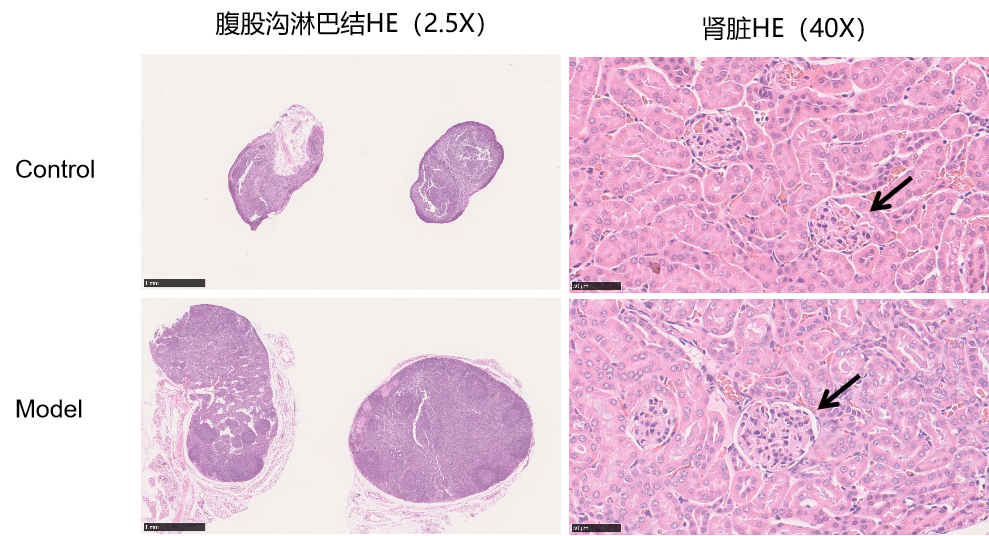

通过降植烷诱导BALB/c小鼠以构建SLE模型,在造模第6个月后,小鼠腹股沟淋巴结、脾脏明显增大,面背部脱毛,存在明显的系统性红斑狼疮症状。

图5 小鼠表型、淋巴结、肾脏及脾脏变化

图6 H&E染色